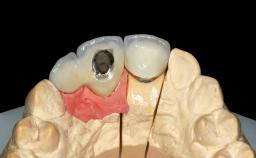

Replacement of Two Central Incisors with Non-Splinted Crowns on Bone-Level Implants

A 27-year-old female patient was referred to the Clinic of Oral Surgery and Stomatology of the University of Bern due to acute pain in the region of her two maxillary central incisors. The patient was in good general health. She reported a bicycle accident approximately 5 years earlier in which teeth 11 and 21 had been traumatized but neither fractured nor displaced. Several weeks after the accident, endodontic treatment was performed on both central incisors, although the patient did not recall the precise reasons for this decision. About 2 years ago, non-vital bleaching had been conducted, in accordance with the “walking-bleach” principle, due to progressive discoloration of teeth 11 and 21.